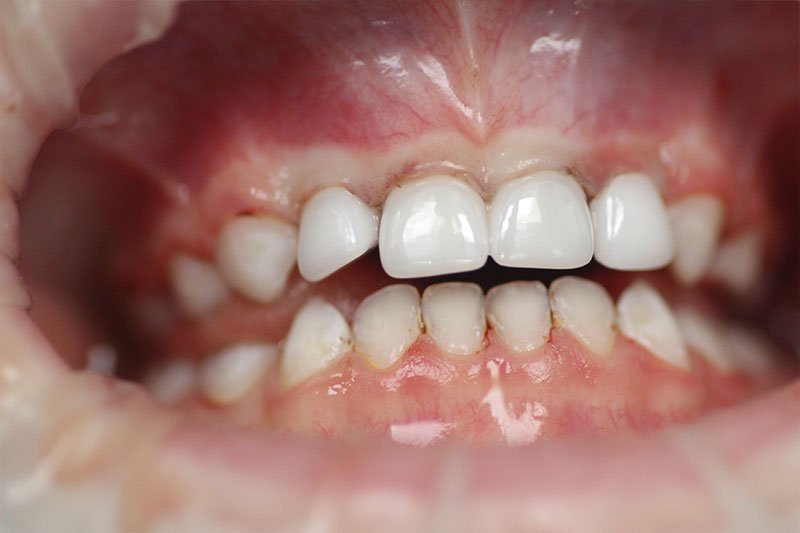

Get the bright white smile you’ve always wanted! Contact us today to get your $139 whitening trays.